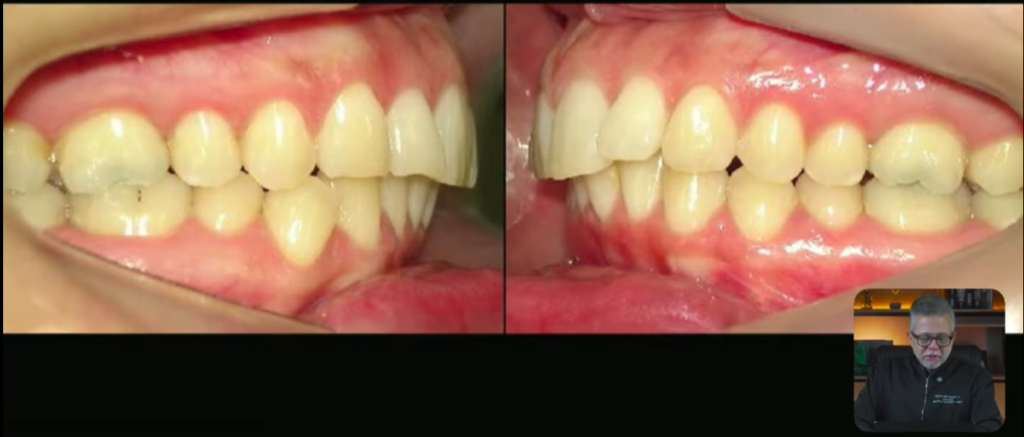

Essas fotos aqui são o antes e o depois, então aqui nós tínhamos a paciente biprotrusa e depois das 4 extrações ela ficou com os incisivos bem posicionados:

Vejam a mudança que aconteceu

vamos imaginar que eu vou fazer o tratamento da classe 2, e essa paciente ela tem uma classe 2 unilateral:

Quando eu vou fazer o tratamento dessa classe 2, eles estão em uma posição ideal, eles estão bem posicionados, o superior ele está quase tangenciando a órbita, o incisivo superior está levemente lingualizado:

Esse inferior está quase bem posicionado,

só que deu para observar que tanto o superior quanto o inferior, o superior está levemente lingualizado e o inferior está levemente vestibularizado: